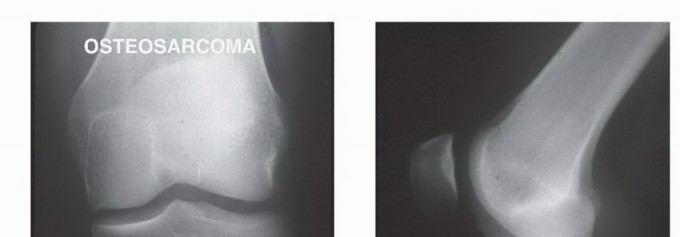

صورة شعاعية تظهر ساركوما عظمية في قصبة الساق القريبة لمريضة تبلغ من العمر 17 عاماً.

صورة شعاعية توضح ورماً عظمياً في قصبة الساق القريبة.

صورة شعاعية جانبية توضح ساركوما عظمية في قصبة الساق القريبة.

صورة شعاعية تظهر تدميراً قشرياً وامتداداً للأنسجة الرخوة للورم.